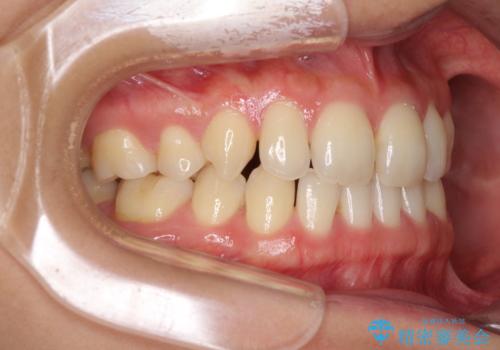

- 以前の矯正治療の後戻りにより、上の前歯にスペースができたことを気にして来院された患者様です。

インビザラインを用いて前歯のスペースを閉じつつ、上下の咬み合わせを構築していくこととしました。

隙間の空いてしまった前歯は、矯正治療で治療を行っても後戻りが起こりやすい傾向にあります。

マウスピースの保定装置をしっかりと装着しても空いてしまうため、細いワイヤーによる保定を併用することで後戻りを防止しています。